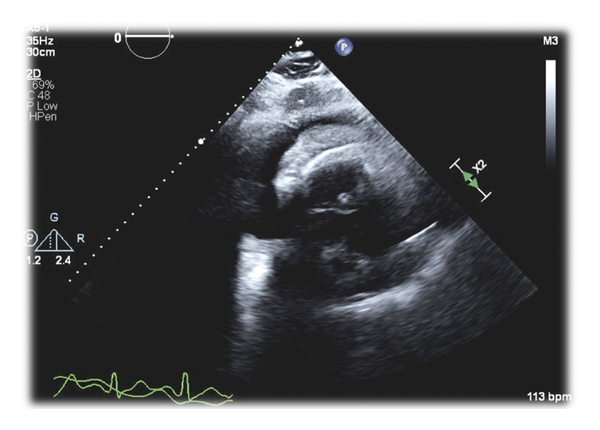

On admission, the patient was tachycardic, tachypneic, and hypoxic. Exam was notable for saddle nose deformity, distant heart sounds, jugular venous distention, and an AV fistula bruit. Lab examinations revealed normocytic anemia, elevated BUN (56 mg/dL) and Cr (12.3 mg/dL), hyperkalemia, hypophosphatemia, elevated acute phase reactants (ESR 91 and CRP 46.98), elevated α1 and α2 globulins, and increased κ and λ free light chains. Further workup showed negative c-ANCA, positive p-ANCA, elevated myeloperoxidase antibodies (>8 U), normal serine protease 3 antibodies (<0.2 U), and normal complement levels. EKG showed sinus tachycardia with S wave in lead I, Q wave in lead III, and electrical alternans (Figure 1). CTA was negative for pulmonary embolism but revealed a moderate pericardial effusion and bilateral pulmonary opacities (Figure 2). Subsequent echocardiogram was consistent with tamponade with a solid component in the effusion (Figure 3).

The patient received emergent dialysis and a pericardial window. Pericardial fluid was bloody, and pericardial tissue pathology showed acute inflammation, granulation tissue, and fibrinopurulent exudate. He was prescribed pulse dose steroids with a taper and plan for outpatient follow-up for cyclophosphamide initiation. Unfortunately, our patient was rehospitalized within a month of discharge for occlusion of his AVF and sepsis from CMV colitis and E coli bacteremia. He sadly passed away secondary to cardiogenic shock and hypoxic respiratory failure during this hospitalization.